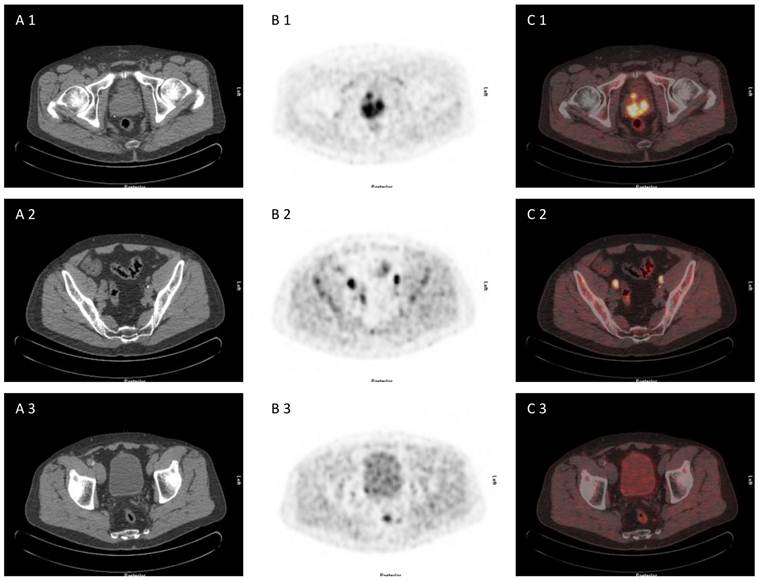

Fig 2

71 year old patient with biopsy proven prostate cancer, initial PSA 193 ng/ml, referred for [18F]choline PET/CT for primary staging. [18F]choline PET/CT revealed adcanced disease (primary prostate cancer, iliacal and pararectal lymph node metastases) (A 1-3) CT scan, (B 1-3) PET scan, (C 1-3) PET/CT fused images.